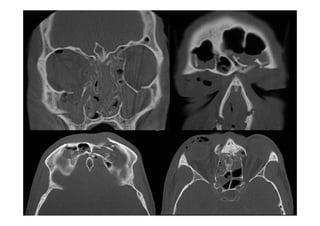

Fracturas del Complejo Naso-

Etmoido-Maxilo-Fronto-Orbitario

Fracturas Cigomáticas Complejas

Fracturas Órbito-craneanas